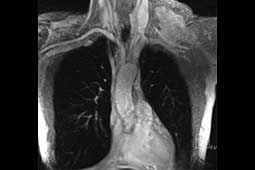

A 70-year-old male presented with a 16-month history of cervical and left shoulder pain. Computed tomography showed an oval solid lesion measuring 10 x 6 x 5.5 cm in the left lateral cervical space. An incisional biopsy revealed that the mass to be a low-grade spindle cell tumor compatible with DT. Magnetic resonance imaging of the neck and thorax showed an encapsulated lesion in the left lateral cervical region with marked contrast enhancement. The subclavian vessels and the brachial plexus were dislocated anteriorly, apparently not infiltrated by the mass (Figure 1).